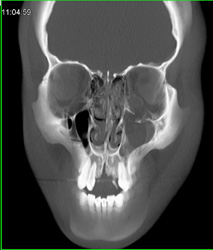

Orbital Fracture